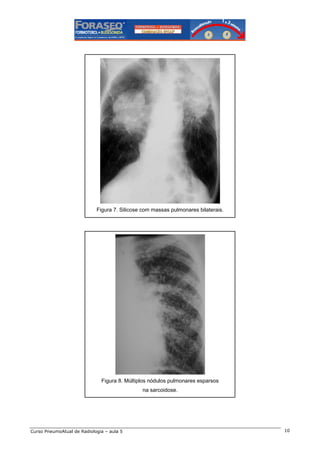

Outras causas menos freqüentes de nódulos pulmonares são a silicose (figura 7), a sarcoidose (figura 8) e

as vasculites.

Figura 7. Silicose com massas pulmonares bilaterais.

Figura 8. Múltiplos nódulos pulmonares esparsos

na sarcoidose.